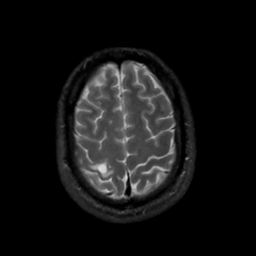

MR Study #7, March 24, 1991 -- Slice #41